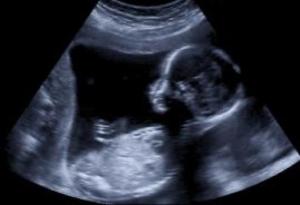

Genom att sända ut ett ljud och att det studsar tillbaka kan vi titta in i människokroppar och även ner i vattnet. Med en ultraljudsapparat så kan man skicka ut och ta emot ultraljud så när ljudet studsar så kan apparaten mäta avstånd och även få fram en bild på det ljudet studsar emot. En ultraljudsbild av ett barn kan se ut såhär:

Ultraljudet används till mycket men de flesta vet vad ultraljud är pga att man gör ultraljudskontroller när man är gravid där man kan se så att bebisen mår bra, om det är tvillingar eller inte eller om det är en tjej eller kille.